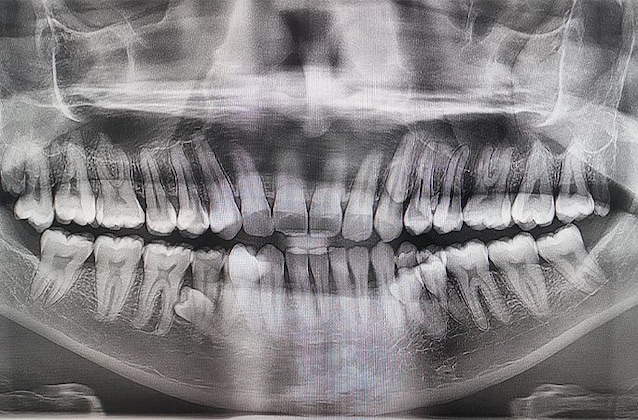

Ma com'è possibile che Prathab Muniandy possieda così tanti denti? Si tratta di una condizione definita “iperdonzia” che, come evidenziato in questo studio scientifico, è una delle più frequenti anomalie dentali, caratterizzata da denti in eccesso rispetto al numero normale (definiti “denti soprannumerari“) che possono essere presenti sia nell’arcata mascellare che in quella mandibolare.